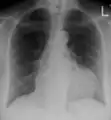

The diagnosis of tamponade can be confirmed with trans-thoracic echocardiography (TTE), which should show a large pericardial effusion and diastolic collapse of the right ventricle and right atrium. Chest X-ray usually shows an enlarged cardiac silhouette ("water bottle" appearance) and clear lungs. Pulmonary congestion is typically not seen because equalization of diastolic pressures constrains the pulmonary capillary wedge pressure to the intra-pericardial pressure (and all other diastolic pressures).

Ultrasounds showing a pericardial effusion in someone with pericarditis A pericardial effusion as seen on CXR in someone with pericarditis

A pericardial effusion as seen on CXR in someone with pericarditis